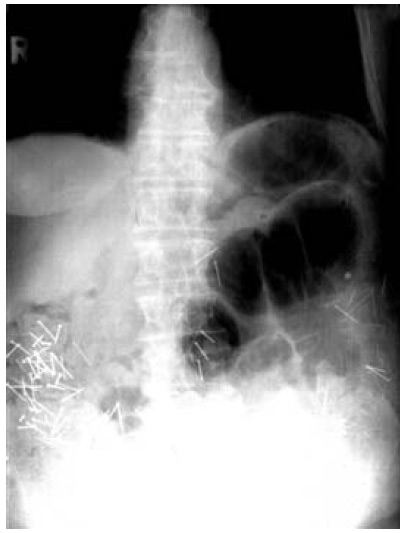

بعد از مراجعه به پزشک در رادیوگرافی که از شکم این فرد گرفته شده است 30 عدد سنجاق ته گرد و 48 عدد میخ در شکم این فرد مشاهده می شود. با درمان دارویی و رژیم غذایی پزشکان موفق به خارج کردن میخ ها و سوزن ها می شوند البته این فرد دو ماه بعد به علت سکته قلبی فوت می کند. متعاقب مرگ این فرد فرزندان وی ضمن شکایت خواستار بررسی علت فوت و بررسی هرگونه ارتباط احتمالی بین مرگ ایشان با اقدامات انجام شده توسط همسر وی می شوند. اما بعد از کالبد شکافی شواهدی که ارتباط میان این دو را ثابت کند به دست نیامد.